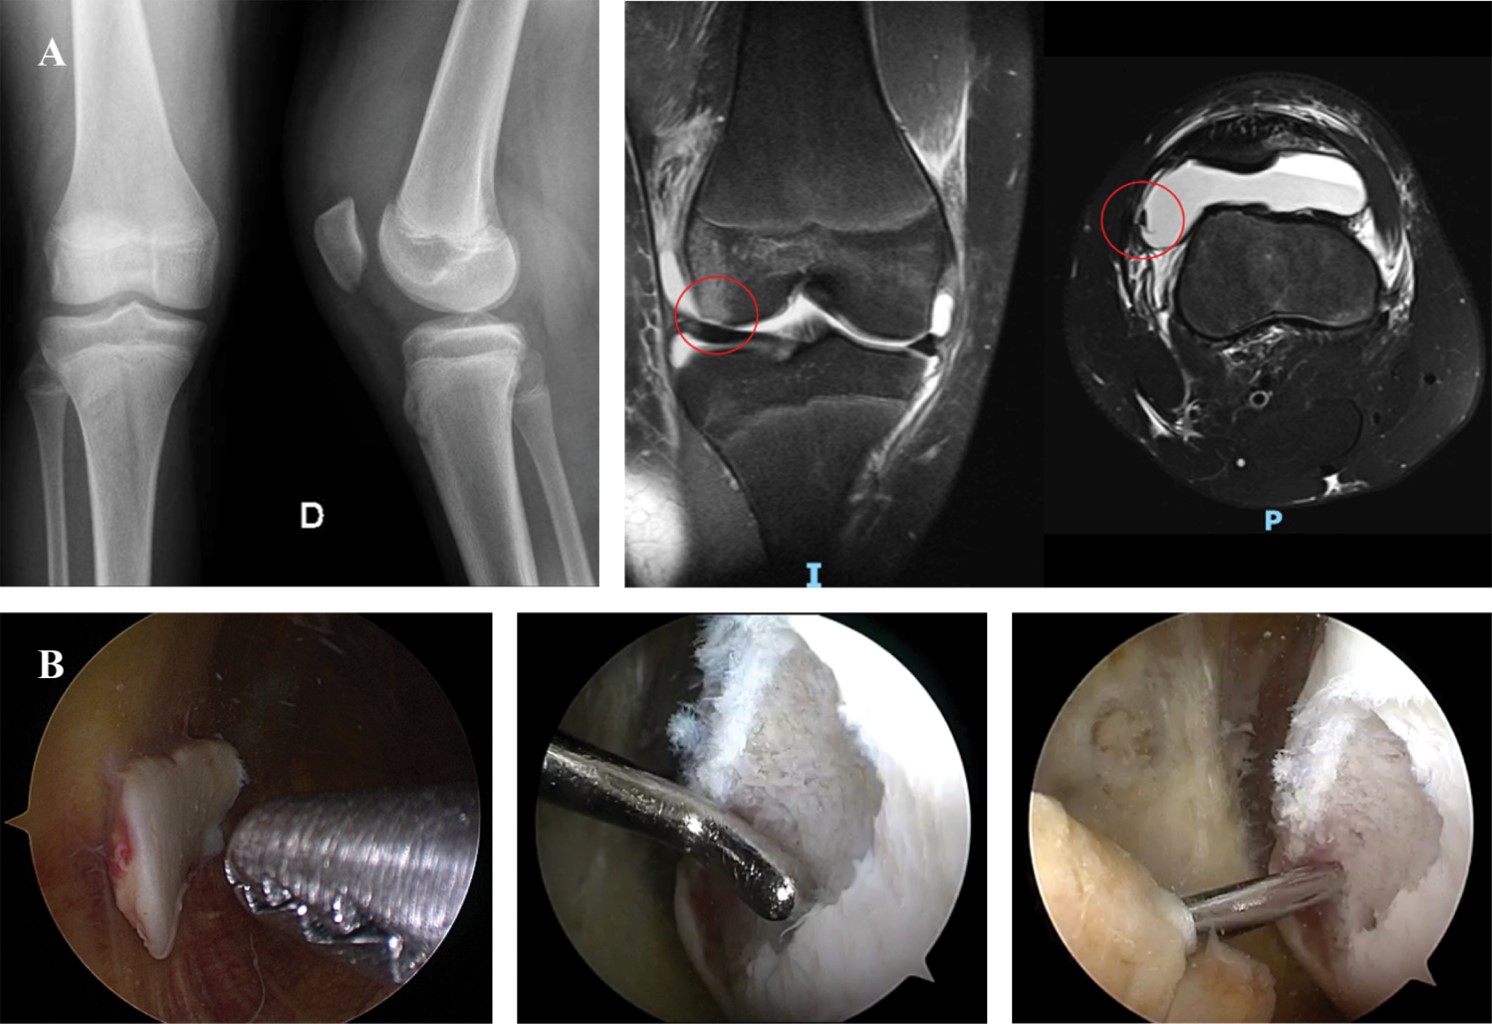

Tibial eminence fractures are epiphyseal avulsion injuries, that typically occur in children from 8 to 14 years of age, and account for 5% of the traumatic effusions around the pediatric knee.6,7 The most common mechanism of injury is a non-contact sports trauma, or falls from bicycle,8 competitive sports, and traffic accidents.9,10 In children, ossification of the proximal tibial leaves the tibial eminence at risk of avulsion as it is cartilaginous. When excessive stress is applied to the ACL the incomplete ossified tibial spine presents less resistance than does the ligament, resulting in a fracture through cancellous bone beneath the tibial spine.4 Patients with TEF may present with knee pain, joint effusion, inability to bear weight and reduced knee range of motion.11 Although most patients can be diagnosed with plain knee radiographs, a high percentage may have associated injuries.12 MRI is valuable to identify associated meniscal tears, collateral ligament, and chondral injuries which can be present in up to 40% of the cases.12,13,14,15,16,17 The Meyers & McKeever classification divides TEF into three types according to the degree of displacement. Further modifications have been described to include comminution and articular involvement (Figure 1).18,19,20

Type I fractures are nondisplaced and can almost universally be treated with a non-weight bearing long leg cast for 3 to 4 weeks. Type II fractures, which are hinged posteriorly with superior displacement of the anterior segment, were also historically treated nonoperatively. However, if the eminence is not appropriately reduced with closed treatment, outcomes may be complicated from lack of extension due to impingement or increased laxity from failure to restore the ACL insertion. Because of these complications, surgical management is typically recommended for type II fractures unless anatomic reduction can be achieved with knee extension and immobilization. Type III and IV fractures are entirely displaced and require surgical treatment.21,22

Surgical treatments range from open surgery to arthroscopy.23 Arthroscopic-assisted fracture reduction and internal fixation has become increasingly popular for the management of articular fractures of the knee, as it has lower morbidity, earlier mobilization and shorter length of hospital stay than those treated with open surgery.24,25 It also allows for simultaneous treatment of associated soft tissue injuries, such as meniscal tears, meniscal and intermeniscal ligament entrapment, intrasubstance anterior cruciate ligament (ACL) tears, and removal of loose fragments. There are several fixation methods available: cortical screws, headless screws, absorbable or nonabsorbable suture, suture anchors, or Kirschner wires. Clinical and radiographic results do not differ in relation to the chosen method of fixation.24 Screws and suture fixation are the most commonly used techniques and they produce reliably satisfactory results. Cannulated screws are associated with anterior impingement, leading to a higher rate of implant removal. One of the advantages of the suture technique is the possibility to treat fractures with different patterns including small or comminuted fragments. Also, sutures can provide a stable fixation with no need for further intervention to remove the implant. Beyond the chosen technique, the ultimate goal must be to obtain the most stable fixation and not cause impingement to allow an early range of motion to prevent arthrofibrosis (most common complication). Risk factors for postoperative stiffness include malunion, prominent hardware, complete fracture displacement, revision, and length of postoperative immobilization.26 Other reported complications include instability,15 non-union, mal-union,22 growth arrest, and pain. Complication rate increases with progression of the Meyers and McKeever classification. Anterior cruciate ligament laxity and/or an extensor lag have been documented after anatomical reduction and consolidation.27,28,29 Despite the laxity, few patients complain of pain or instability.4 Overall prognosis is good with a high rate of successful healing, complete restoration of knee stability and returning to prior level of sport.30